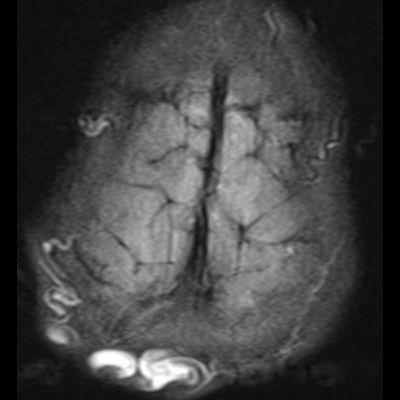

1. A) Kontrastlı FLAIR aksiyel görüntüde ve sagital T2A görüntüde vertekste orta hatta cilt altında dilate tortiyoze vasküler kollateraller (oklar). Paryetal kemikte orta hatta defekt (ok) ve defekt ile ilişkili vasküler yapıların cilt altı yumuşak dokulara uzanımı izlenmektedir.